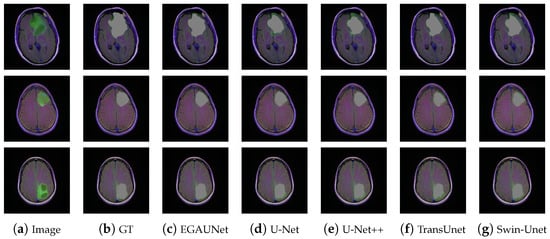

4.3.3. Brain MRI Dataset